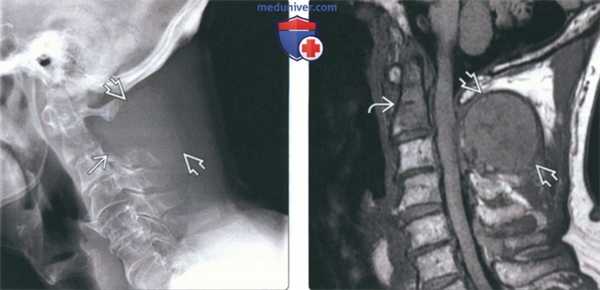

(Слева) На рентгенограмме в боковой проекции у пациентки с распространенным бласти -ческим метастатическим поражением на фоне рака молочной железы определяется диффузный склероз шейных позвонков и основания черепа. Видны наложения от сережек.

(Справа) На сагиттальной MPT (Т1 ВИ) определяются множественные остеобластические метастазы с сигналом крайне низкой интенсивности, свидетельствующим о их бластическом характере. Типоинтенсивный сигнал должен сохраняться и во всех стальных последовательностях.